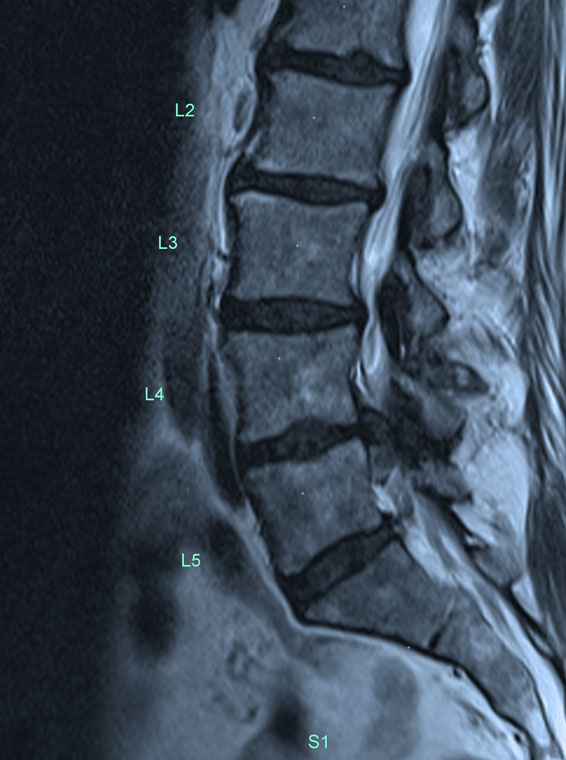

SURGICAL PROCEDURES & CONDITIONS OF THE SPINE

Spine Microdiscectomy

Spine Laminectomy

Spine Anterior Lumbar Decompression And Fusion

Spine Posterior Lumbar Decompression And Fusion

Spine Extreme Lateral Lumbar

Decompression and Fusion